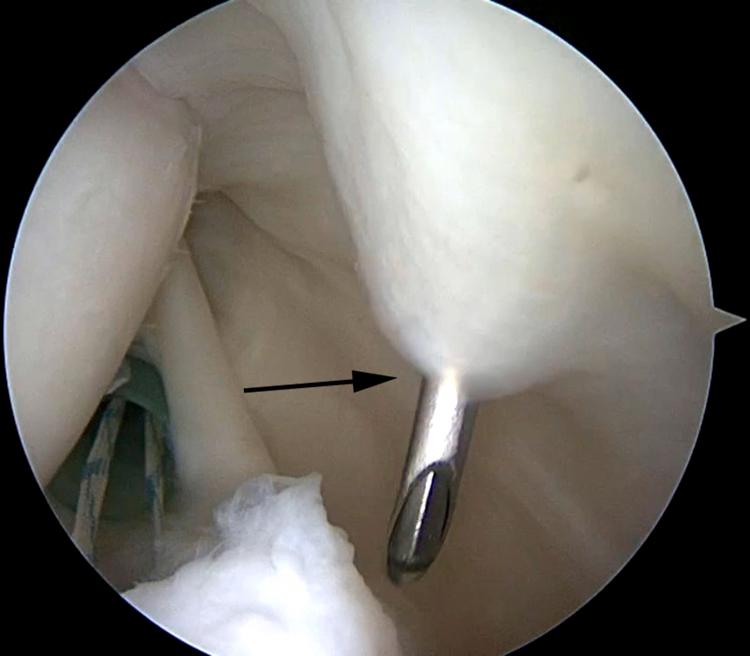

SLAP tears have been a controversial topic in shoulder surgery for decades. The indications for repair of SLAP tears, as well as the methods of repair, have undergone a recent evolution. The use of intra-articular knots for SLAP repair has fallen out of favor because of potential abrasive damage to the rotator cuff and glenohumeral articular cartilage due to knot migration and prominence. In response to this potential iatrogenic injury, arthroscopic techniques have undergone an evolution using advanced techniques with low-profile knotless repairs. We describe our preferred low-profile knotless technique for SLAP repair using LabralTape (Arthrex) in a horizontal mattress configuration.

几十年来,肩袖上盂唇(SLAP)损伤一直是肩部手术中颇具争议的话题。SLAP损伤的修复指征以及修复方法最近都有所发展。由于结的迁移和突出可能对肩袖和肱盂关节软骨造成潜在的磨损损伤,关节内打结用于SLAP修复已不再受青睐。针对这种潜在的医源性损伤,关节镜技术已发展为采用先进技术进行低轮廓无结修复。我们描述了一种使用LabralTape(Arthrex)以水平褥式缝合方式进行SLAP修复的首选低轮廓无结技术。